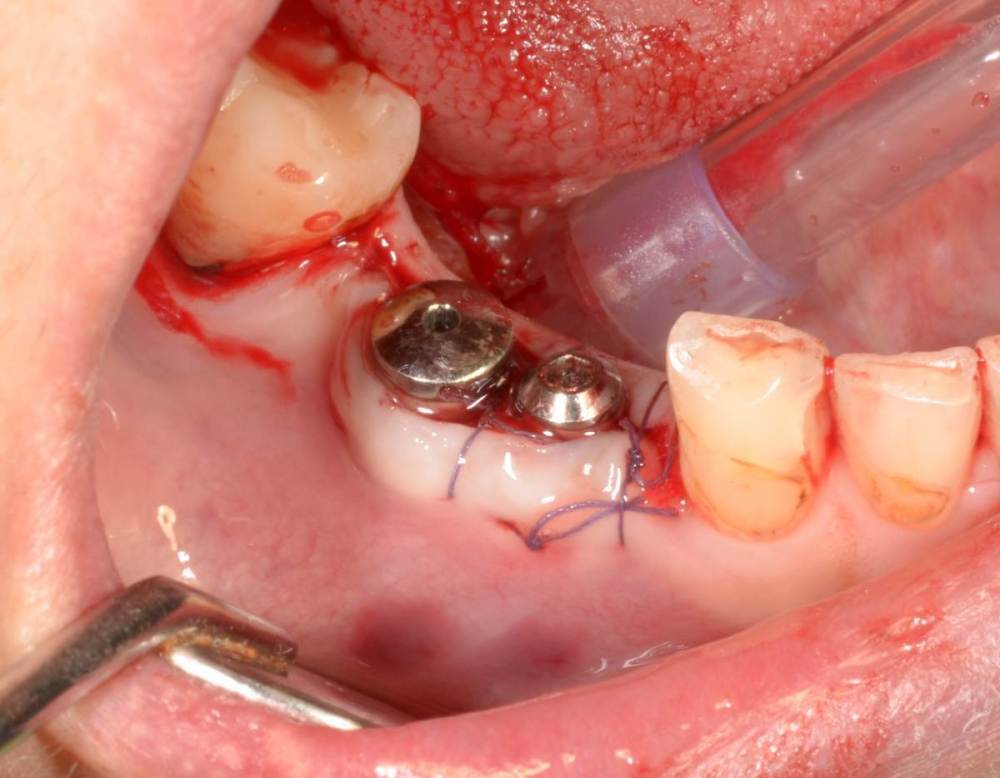

Большой Зеленый Опубликовано 27 мая, 2022 Поделиться Опубликовано 27 мая, 2022 Аналогично..) 4 1 Ссылка на комментарий

Большой Зеленый Опубликовано 27 мая, 2022 Поделиться Опубликовано 27 мая, 2022 Через 9 лет. Есть немного рецессии.. 2 Ссылка на комментарий

Женька Опубликовано 27 мая, 2022 Поделиться Опубликовано 27 мая, 2022 @Большой Зеленый это вроде ваш старый кейс? напомните пожалуйста, тут присыпка+мембранинг вестибулярно и вестибулярным лоскутом слегка послабленным всё закрыли? Ссылка на комментарий

Большой Зеленый Опубликовано 28 мая, 2022 Поделиться Опубликовано 28 мая, 2022 12 часов назад, Женька сказал: @Большой Зеленый это вроде ваш старый кейс? напомните пожалуйста, тут присыпка+мембранинг вестибулярно и вестибулярным лоскутом слегка послабленным всё закрыли? Да все так и есть как Вы и описали. Работе почти 10 лет. Присыпка мп3 от остеобила сверху "ильгамовская" губка . Считаю что результат вполне удовлетворительный. Рецессия обусловлена как уже сказали выше вестибулярным положением импланта ,ну и недозаглублен чуток. Ссылка на комментарий